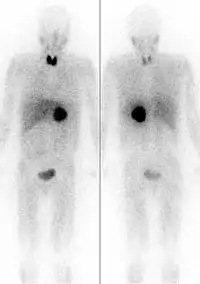

Iodine-131 can be "seen" by nuclear medicine imaging techniques (e.g., gamma cameras) whenever it is given for therapeutic use, since about 10% of its energy and radiation dose is via gamma radiation. However, since the other 90% of radiation (beta radiation) causes tissue damage without contributing to any ability to see or "image" the isotope, other less-damaging radioisotopes of iodine such as iodine-123 (see isotopes of iodine) are preferred in situations when only nuclear imaging is required. The isotope 131I is still occasionally used for purely diagnostic (i.e., imaging) work, due to its low expense compared to other iodine radioisotopes. Very small medical imaging doses of 131I have not shown any increase in thyroid cancer. The low-cost availability of 131I, in turn, is due to the relative ease of creating 131I by neutron bombardment of natural tellurium in a nuclear reactor, then separating 131I out by various simple methods (i.e., heating to drive off the volatile iodine). By contrast, other iodine radioisotopes are usually created by far more expensive techniques, starting with cyclotron radiation of capsules of pressurized xenon gas.[4]

Iodine-131 is used for unsealed source radiotherapy in nuclear medicine to treat several conditions. It can also be detected by gamma cameras for diagnostic imaging, however it is rarely administered for diagnostic purposes only, imaging will normally be done following a therapeutic dose.[38] Use of the 131I as iodide salt exploits the mechanism of absorption of iodine by the normal cells of the thyroid gland.

Iodine-131, in higher doses than for thyrotoxicosis, is used for ablation of remnant thyroid tissue following a complete thyroidectomy to treat thyroid cancer.[41][39]

The 131I isotope is also used as a radioactive label for certain radiopharmaceuticals that can be used for therapy, e.g. 131I-metaiodobenzylguanidine (131I-MIBG) for imaging and treating pheochromocytoma and neuroblastoma. In all of these therapeutic uses, 131I destroys tissue by short-range beta radiation. About 90% of its radiation damage to tissue is via beta radiation, and the rest occurs via its gamma radiation (at a longer distance from the radioisotope). It can be seen in diagnostic scans after its use as therapy, because 131I is also a gamma-emitter.

Diagnostic uses